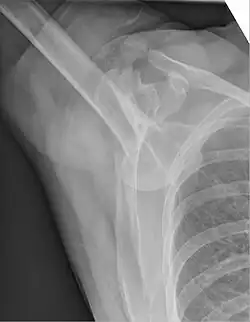

Grundlage ist die Anamnese (Unfallmechanismus) und körperliche Untersuchung (Funktionseinschränkung). Dabei muss insbesondere die Schädigung von Blutgefäßen und Nerven beachtet und dokumentiert werden. Durch Röntgenbilder in verschiedenen Ebenen wird die Diagnose gesichert und eine Fraktur ausgeschlossen. Zum Ausschluss einer Bankart-Läsion (s. u.) kann eine MRT-Aufnahme angefertigt werden.